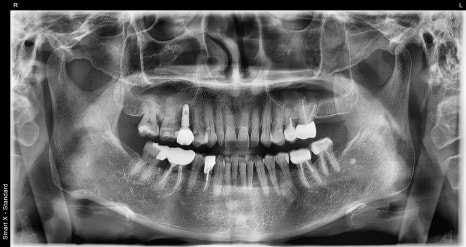

At Seoul Oue Dental Hospital, panoramic imaging and

CT scans are used to check the following:

The thickness and height of the jawbone

The location of nerves

Whether there is existing inflammation

The condition of surrounding teeth

The patient in their 60s also learned through these tests

that “the bone needs to be reinforced before placing the implant.”

Previous image

Next image

This is because the amount, structure, and gum condition of the bone

are different for each patient.